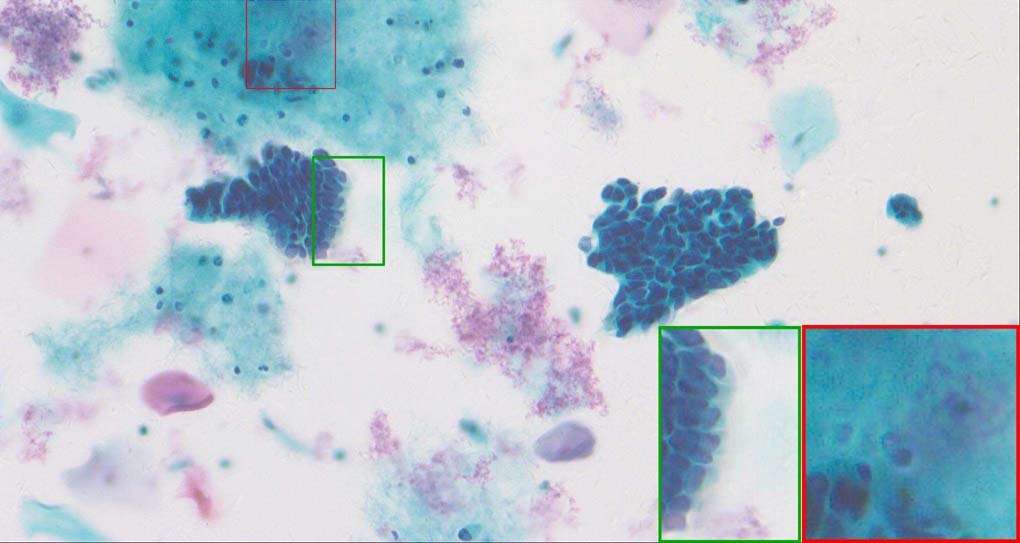

A good image fusion method should contain the following properties. First, it preserves both the details of small size objects and the integrity information of large size objects in the fused image, even in the case of the size of the interested objects varying largely in the image. For example, the cervical cell images from the microscope contain both small size isolated cells and large size agglomerates, which are both useful for cervical cytology [5]. Second, it should be efficient enough to handle large-scale data. For instance, it needs to process thousands of fields of view (FoV) in an acceptable time for the whole slide scanning in digital cytopathology [6], which requires to fuse a series of high resolution images captured at each FoV in a very efficient way. Third, it does not produce obvious artifacts. Despite being studied extensively, to our best knowledge, existing fusion methods may not meet these requirements simultaneously.

To demonstrate the effectiveness and efficiency of the proposed image fusion method , we conduct a set of comparative experiments on three image datasets. The first is composed by 8 pairs of multi-modal medical images and the second one contains 15 pairs of multi-focus gray or color natural images. These two datasets are often used in many related papers and some examples are shown in Figure 3(a) and Figure 3(b). The third one is a new multi-focus cervical cell image dataset collected by ourselves, which consists of 15 groups of color images and each group contains a series of multi-focus cervix cell images with size of or , etc. Some source examples are shown in Figure 3(c). Our source code implemented in C++ along with the new multi-focus cervical cell image dataset is available online.

Figure 9, Figure 10 and Figure 11 show the comparative fused results of the multi-focus cell images shown in Figure 3(c). For clarity, we also present a closeup view in the right-bottom of each sub-picture in Figure 9 and Figure 10. As shown in the close-up views of Figure 9, the fused images based on DSIFT, IM, MWGF and BF methods are extremely blurred in the boundary and fail to keep the details of cell nucleus. Furthermore, the DTCWT and NSCT based methods produce halo artifacts in the fused images, while GFF and CNN based methods fail to preserve the small cell nucleus. LP-SR based method nearly works fine which keeps the most of the details of the small size cells, but the integrity of the clustered large size cells is damaged. Fortunately, in our proposed method, the integrity of the clustered large size cells is preserved and most of the isolated small size cells are maintained from the original images, which demonstrates the best visual quality.